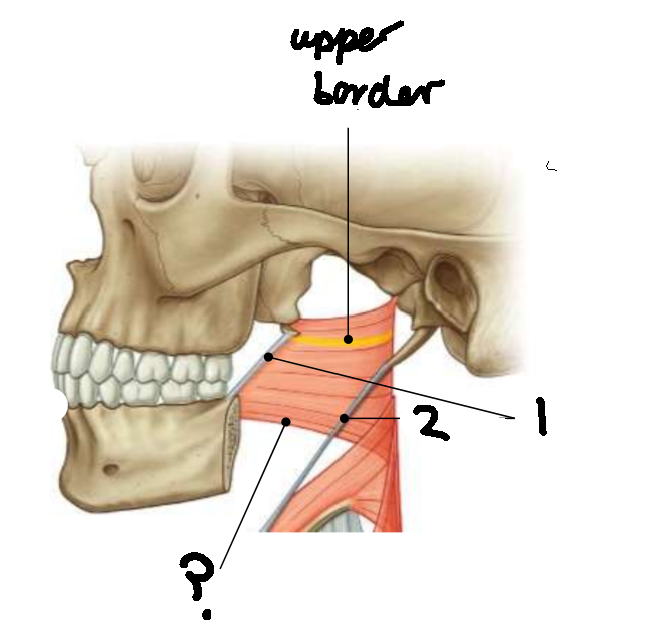

What muscle is this?

superior constrictor

What is the upper border of this muscle?

palatopharyngeal sphincter

What is 1?

pterygomandibular raphe

What is 2?

stylohyoid ligament

What are the attachments of this muscle?

pterygoid hamulus, pterygomandibular raphe, posterior end of mylohyoid line → pharyngeal raphe